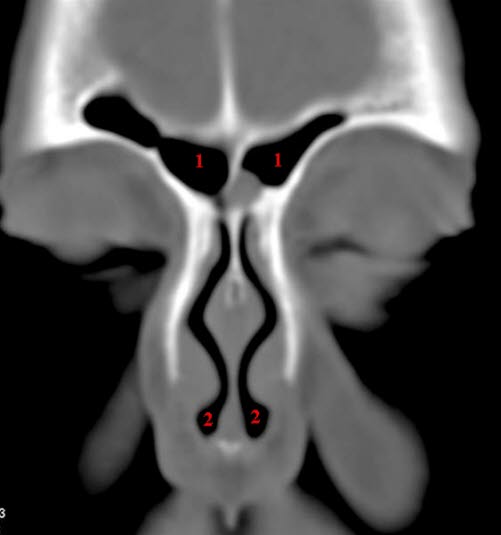

Frontalsinus, coronal

CT-snitt i coronalplan gjennom frontalsinus (1) og fremre deler av nesen (2)